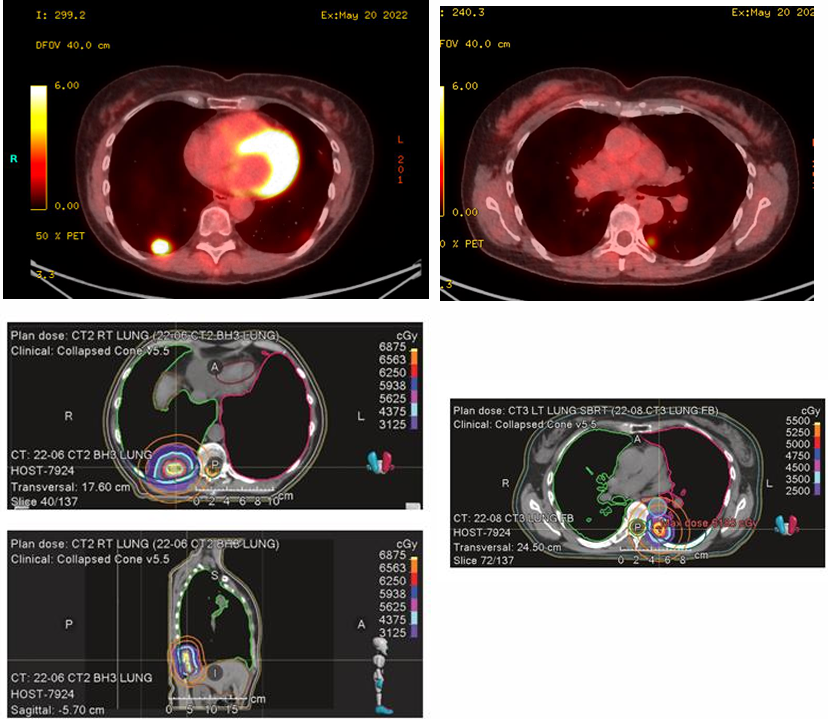

2023年9月,患者开始使用Adagrasib,针对KRAS G12C突变。然而,PFS仅为11个月,左下肺叶结节出现进展。团队采用质子治疗,剂量为60Gy,分12次照射。2024年6月,患者纵隔淋巴结和右肾上腺出现寡进展,再次接受质子治疗,剂量分别为45Gy(分15次)和40Gy(分5次)。这表明,精准医疗在控制寡进展病灶方面具有显著优势,但其疗效可能受肿瘤生物学特性等多种因素影响。

a457c443-7cad-47a7-bc8d-cf459ba01e3f.png

整个治疗过程中,肿瘤委员会多次参与讨论,为患者的治疗方案提供重要指导。在2022年6月和2024年6月,团队基于患者的影像学进展和生物标志物检测结果,分别推荐SBRT和质子治疗方案。此外,团队还考虑患者的治疗意愿和辅助治疗需求,如在质子治疗期间暂停Adagrasib,并根据患者的生活计划调整治疗方案。这强调多学科协作在制定个性化治疗方案中的重要性,以及患者参与治疗决策的必要性。